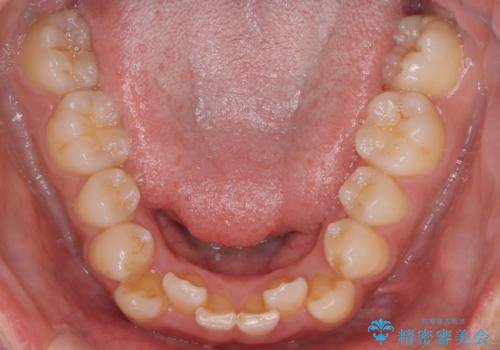

反対咬合と前歯のガタガタを非抜歯で改善

- 患者様は、上下の前歯のガタガタと反対咬合(下の歯が上の歯より前に出ている状態)を主訴として来院されました。診断の結果、抜歯を行わずに治療を進めるため、臼歯を遠心移動させてスペースを作り、IPR(インタープロキシマルリダクション)で歯間を調整する治療計画を立てました。インビザラインを使用して、透明で目立たない矯正装置により、歯列を整えながら噛み合わせも改善することを目標としました。

非抜歯での治療では、限られたスペースの中で効率的に歯を動かす必要があります。本症例では、臼歯を後方に移動させる遠心移動を行い、歯列のガタガタを改善しました。また、IPRを適切に行うことでスペースを確保し、歯根や歯肉への負担を最小限に抑えながら治療を進めました。インビザラインを使用することで、治療中も目立ちにくく、患者様の日常生活への影響を軽減しました。結果として、抜歯を行わずに美しい歯並びと自然な噛み合わせを実現し、患者様には大変満足していただけました。